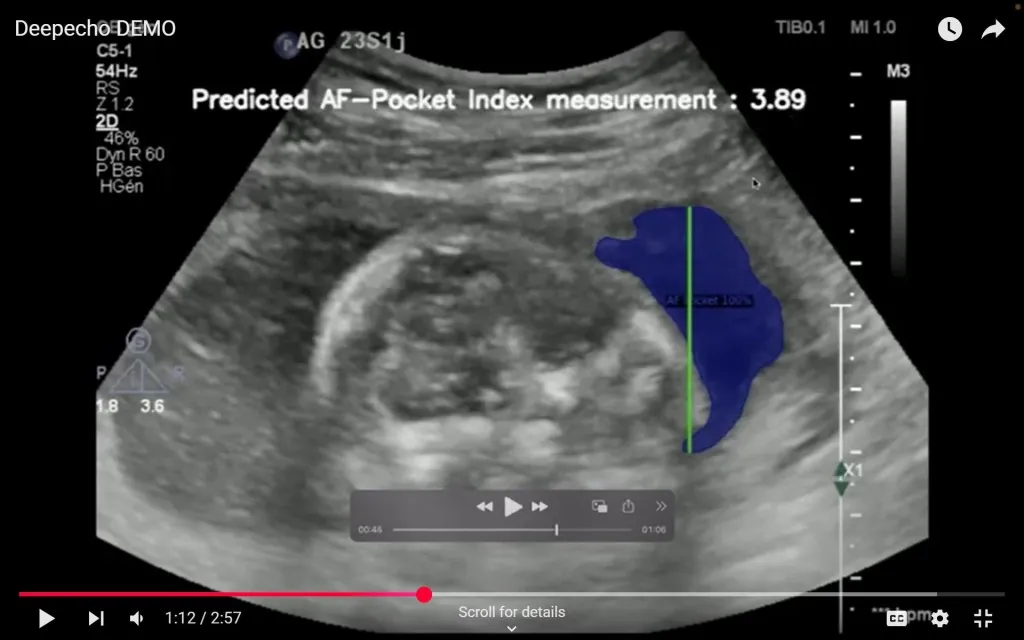

AAIC Investment Pte. Ltd.(本社:シンガポール、代表:椿 進、以下「AAIC Investment」)が運営するアフリカのヘルスケア分野に特化した投資ファンド「Africa Innovation & Healthcare Fund II(以下、AHF2号)」を通じて、DeepEcho(本社:モロッコ、CEO:Youssef Bouyakhf)へ出資しました。 DeepEchoは、AIを搭載した胎児超音波解析プラットフォームを開発・提供しています。また、同社は、2025年6月に米国食品医薬品局(FDA)より510(k)※クリアランスを取得しました。自社のAIが臨床現場レベルで95%以上の認識精度を実現していると公表しており、熟練した医療従事者と同等の信頼性を備えていることを示しています。今回の認可により、米国市場での製品販売と導入が可能となるだけでなく、その技術の安全性と有効性が国際的に認められたことを意味します。今後、医療人材が不足するアフリカをはじめとするグローバルサウスにおける普及に向け、重要なマイルストーンとなります。 DeepEchoのAI技術は、胎児の頭部や腹部、羊水などの各部位を映した超音波画像をリアルタイムで自動的に認識・分類するもので、診断に必要な“標準ビュー”を瞬時に特定します。世界最大級の胎児超音波画像データを学習に活用しており、医師による診断の精度向上と作業の効率化に貢献しています。また、構造を明確に区別するセグメンテーション処理により、より標準化された解析が可能です。 同社は、Googleが主催するスタートアップアクセラレーター「AI First MENA & Turkey」にも選出されるなど、国際的にも高く評価されています。現在提供中の標準ビュー認識および自動解析機能に加え、次世代技術としては新たなバイオマーカーをAIで同定し、子癇前症(preeclampsia)などの複雑な妊娠合併症の早期予測を目指しています。これにより、早期の医療介入と母子の健康改善が期待されます。 さらに同社は、日系企業との連携機会も積極的に模索しており、2025年8月に横浜で開催されるTICAD(アフリカ開発会議)に合わせて、CEOの来日を予定しています。

デモ写真:同社提供